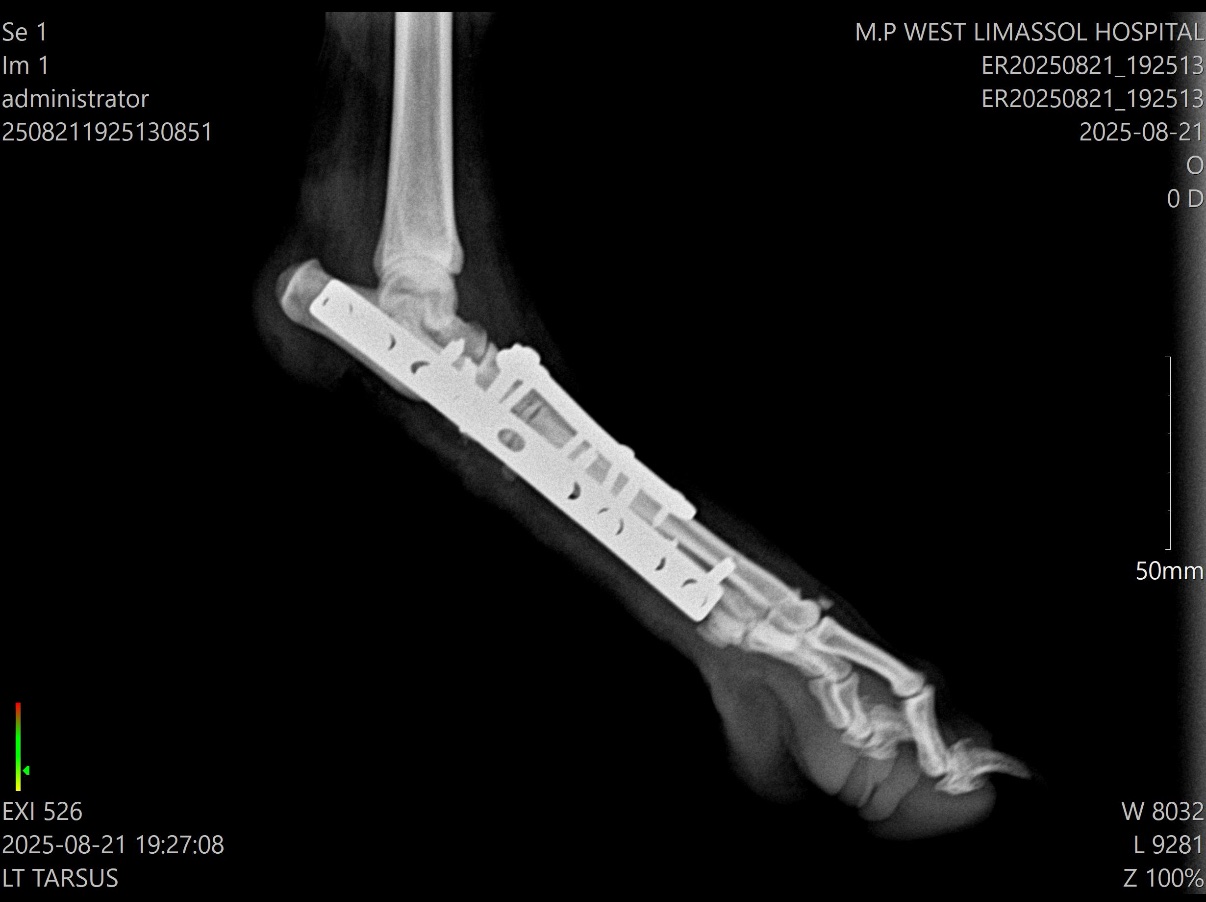

Σχεδιάστηκε μερική αρθρόδεση του ταρσού με σκοπό τη σταθεροποίηση των κατεστραμμένων αρθρώσεων και ταυτόχρονη διατήρηση της λειτουργίας της ταρσοκνημικής άρθρωσης, η οποία είναι απαραίτητη για την απόδοση σε σκύλους εργασίας και άθλησης. Η χειρουργική προσπέλαση περιλάμβανε καθαρισμό των αρθρικών επιφανειών και σταθεροποίηση με δύο πλάκες, τοποθετημένες στρατηγικά ώστε να εξασφαλίσουν μέγιστη βιομηχανική σταθερότητα και να ευνοήσουν την οστική πώρωση. Η χρήση διπλής πλάκας πρόσφερε αυξημένη ακαμψία, μειώνοντας τον κίνδυνο επιπλοκών όπως θραύση υλικών ή καθυστερημένη πώρωση.

Η επέμβαση ολοκληρώθηκε χωρίς επιπλοκές και ο ασθενής ανένηψε ομαλά από την αναισθησία. Η μετεγχειρητική απεικόνιση επιβεβαίωσε τη σωστή θέση των υλικών και την ικανοποιητική ευθυγράμμιση της άρθρωσης. Κατά τη φάση ανάρρωσης εφαρμόστηκε περιορισμένη δραστηριότητα και ελεγχόμενη άσκηση ώστε να διευκολυνθεί η οστική επούλωση με ελάχιστη φόρτιση των υλικών.

Στους επανελέγχους, ο σκύλος έφερε προοδευτικά βάρος στο χειρουργημένο άκρο, με εμφανή βελτίωση της σταθερότητας και της άνεσης. Η πώρωση των αρθροδεδεμένων διαρθρώσεων επιβεβαιώθηκε ακτινολογικά. Η διατήρηση της ταρσοκνημικής λειτουργίας συνέβαλε στη σχεδόν φυσιολογική μηχανική βάδισης. Ο ασθενής αναμένεται να επιστρέψει πλήρως στη δραστηριότητα κυνηγιού κατά την επόμενη περίοδο.